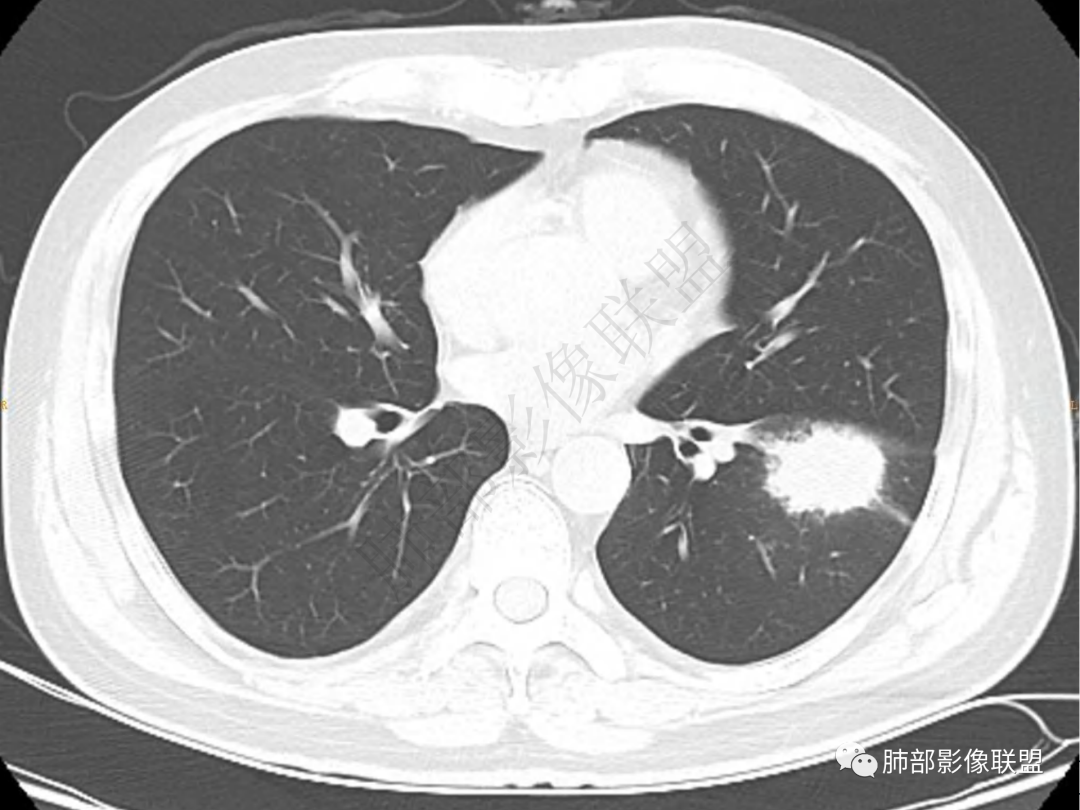

2.左肺下叶团片影,跨背段及内前基底段,实性部分类椭圆形,密度不甚均匀,可见毛刺及棘状突起,未见典型分叶及胸膜凹陷。病灶上下缘可见相应肺段支气管旁进侧出,管壁轻度增厚,未见狭窄阻塞。

3.周边较大范围磨玻璃影,边界相当模糊,小叶增厚明显。注意叶裂另一侧、左肺舌段亦可见磨玻璃影及增厚的小叶间隔。未见明确卫星病灶。

4.实性部分不均匀环形强化并显示一小范围低密度坏死区或空洞。较之肺窗,整体纵隔窗范围较小,提示病灶并不十分密实。抑或为不同时段图像。

一、与胸膜关系:

肺脓肿:可宽基底与胸膜相连,附近胸膜增厚——炎性特点

二、形态、边缘:

肺脓肿:边界模糊不清,或者块影为类圆形,无明显分叶,边缘平直为主,刀切征——炎性特点三、病灶周围特点:肺脓肿:病灶非远端有片状GGO——炎性特点四、近端支气管阻塞:肺脓肿:常有引流支气管伴管壁增厚或者支气管沿洞壁走行。五:坏死壁:肺脓肿:大多壁厚,少数壁薄,没有壁结节,内壁清楚光整——炎性特点